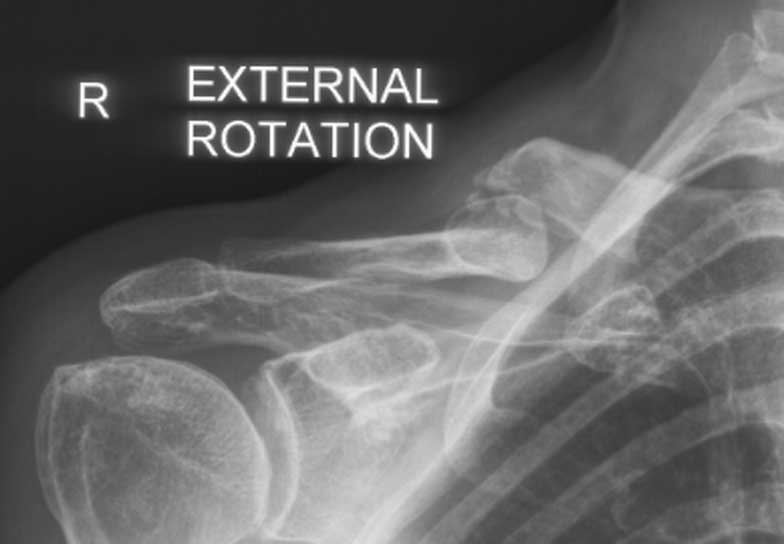

This man is 38 years old and originally fractured his clavicle when much younger. It was left to heal naturally but unfortunately healed in a poor position. He fell while playing soccer and fractured through the previous mal-union and callus. He had surgery and within just six weeks was almost healed and had a good range of motion, function and strength.

Malunion fracture before surgery

Malunion fracture after surgery

Move the slider to compare before surgery and 6 weeks after surgery